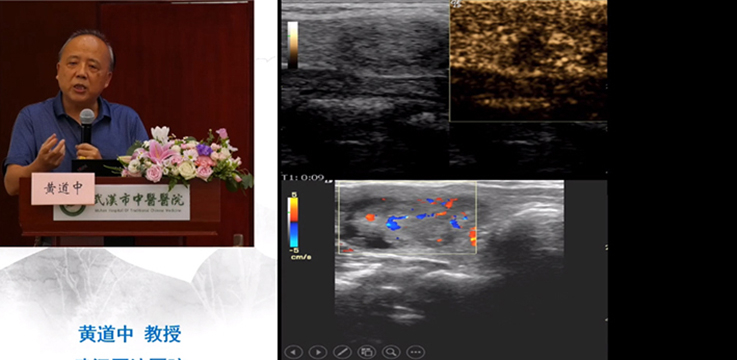

• 醫學直播 武漢市中醫醫院漢陽院區 超聲造影與介入的臨床應用

主辦單位:武漢市中醫醫院漢陽院區超聲診斷科

會議時間:2021年7月16日

會議地點: 武漢市中醫醫院漢陽院區

7月16日下午,由武漢市中醫醫院漢陽院區超聲診斷科舉辦的市級繼續教育項目“超聲造影與介入的臨床應用”學習班在武漢市中醫醫院漢陽院區七樓學術報告廳圓滿舉行。根據疫情防控的要求,這次會議在網上實時同步直播,線上線下參會人數共計八百余人次。思非電子全程提供直播服務。

武漢市中醫醫院王雷副院長出席開幕式并致辭,華中科技大學附屬協和醫院超聲醫學科主任謝明星教授,線上發表講話。武漢市中醫醫院漢陽院區超聲診斷科主任彭國平主持了本次會議。

會上黃道中教授、楊順實教授、余曉梅教授、曾書娥教授、彭國平教授、閔潔醫師作了主旨演講,分享了他們的經驗,并同各位學員進行了案例討論。